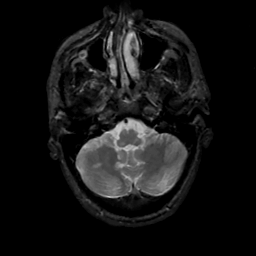

MR Study #12, May 12, 1991 -- Slice #9

[Home][Help][Clinical][Tour 1][Tour 2] Slice 9